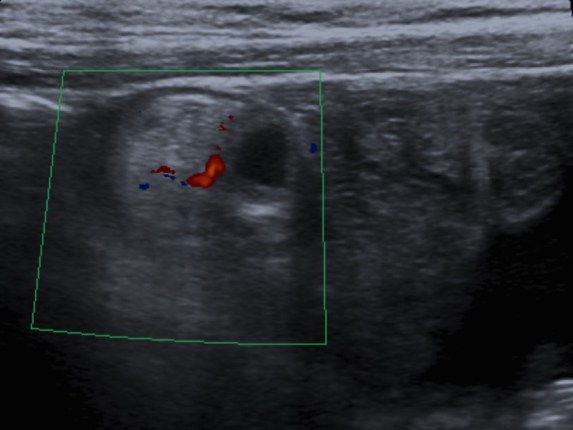

Se realiza ecografía de abdomen. Se observa:

Puede observarse también como una estructura quística con paredes que recuerdan asas intestinales: banda hiperecoica que correspondería a la mucosa y otra banda hipoecoica que correspondería a la muscular. Han sido confundidos con quístes de duplicación (los cuales tienen sin embargo márgenes más regulares). La señal Doppler color puede muestran hiperemia como signo de inflamación del diverticulo.